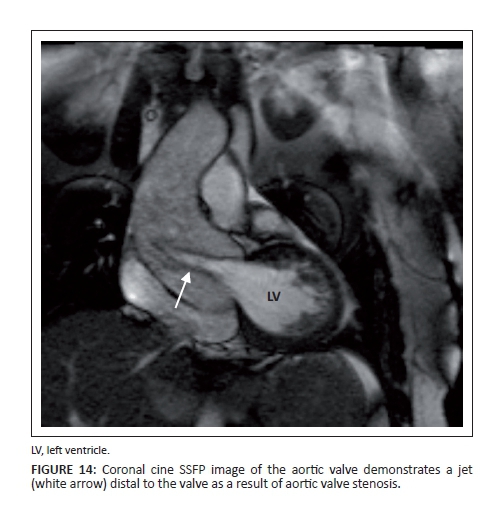

Stenosis

In patients with valvular stenosis, dephasing or a flow jet can be seen distal to the valve (Figure 14). Smaller openings, characteristic of severe disease, cause more dephasing and a darker jet is seen. The phase contrast images in severe stenosis will also demonstrate higher velocities, which will be seen as an area of complete signal loss owing to aliasing if it is above the programmed maximum velocity. This will result in an underestimation of the peak velocity as velocities higher than the programmed maximum velocities cannot be detected. In these instances, the programmed maximum velocity needs to be adjusted until the aliasing artefact disappears. The area of maximum opening of the valve can also be measured on the axial SSFP cine images through the valve (Figure 15).